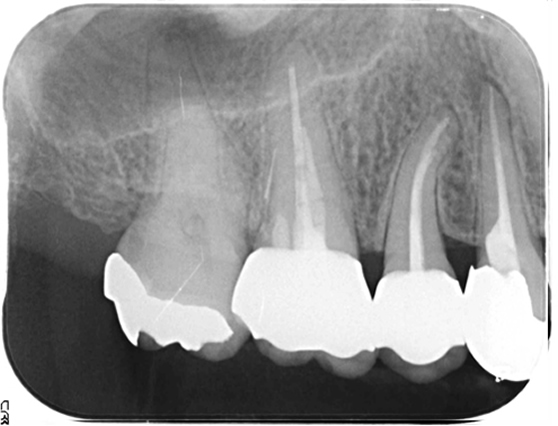

右上4番(右から2番目の歯)を再治療したが治らないとのことで来院。診査したところ、原因は右上5番(右から3番目)の歯の神経が死んでしまっていたためでした。右上5番は通常通り根管治療を行いました。

同時に右上6番に違和感を感じているとのことでしたが、右上6番には歯の横に穴があいており、破折器具が残っている状態でした。破折器具を除去し、根管治療を行いました。(骨内に残った器具は感染源となっておらず、症状が完全に消失したため外科を避けて経過観察としました。その後1年半の経過観察で良好な経過を送っています。